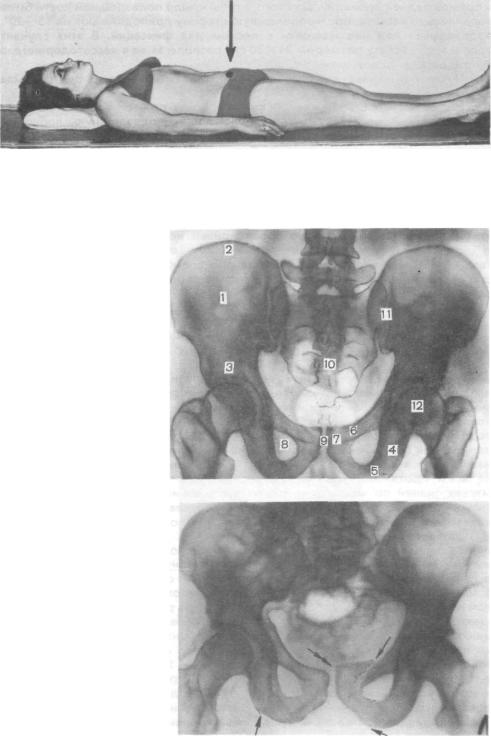

Компьютерная томография органов малого таза: оборудование и результаты исследований